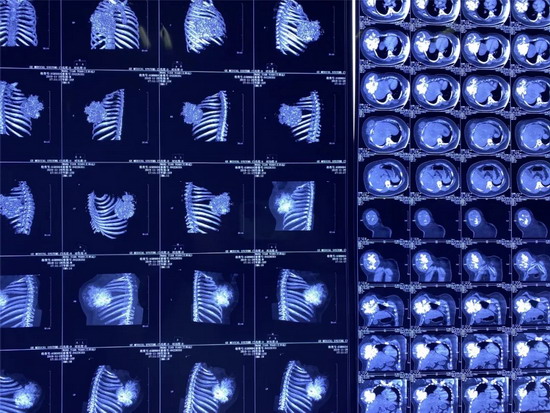

经专家的推荐,家人带着王某来到唐都医院胸腔外科就诊,CT检查显示右前胸壁肿瘤45×35厘米,穿刺活检结果为肋软骨源性恶性肿瘤。由于患者的软骨肉瘤恶性程度高,对放、化疗都不敏感,且易复发,手术切除是首选方案。此外,考虑到患者要切除五根肋骨,术后右前胸壁缺损大,医生决定采用3D打印技术,为王某进行胸廓重建。

2019年10月,王某来到了江苏省东台市某医院做了胸部CT检查。检查结果显示:王某右侧胸壁长了一个外径约45cmX36cm的巨型肿瘤,其右前肋骨骨质已经遭到破坏,医生考虑是软骨肉瘤。

6小时完成5.10公斤超巨大软骨肉瘤切除并做胸内骨植入

“患者是本月9号入院,我们通过B超引导下为患者进行了右前胸壁肿瘤穿刺活检,病理诊断为软骨源性恶性肿瘤—软骨肉瘤。这个手术还是比较棘手的,首先,患者比较年轻,其次,胸壁上的原发性骨肉瘤相对比较罕见;另外,这个肿瘤的切除范围很大,需要胸壁重建,还要不影响患者的正常呼吸。”空军军医大学唐都医院胸外科副主任黄立军介绍,经我们全科医生讨论,软骨肉瘤属来源于间叶组织恶性肿瘤,恶性程度高,易复发,对放疗、化疗不敏感,我们的首选治疗方案是手术切除肿瘤。但是在手术方案的设计上,想要将肿瘤完全切除以防复发和转移,必须切除位置距离肿瘤切缘3 cm以上,也就是说切除的范围到达直径45㎝,而且由于肿瘤巨大,术后患者的右侧前胸壁缺损很大,需要进行胸廓重建,最后,我们为患者用了3D打印钛合金弹性肋骨。术前准备就绪后,我们10日为患者在全麻下进行了6小时的胸壁肿瘤扩大切除,最后完整切下来的肿瘤净重5.10Kg,未发现肿瘤细胞,手术非常顺利,患者术后生命体征平稳,恢复的很好,马上也要出院了。

2019年10月,王某来到了江苏省东台市人民医院,做了胸部CT检查。检查结果显示:王某右侧胸壁长了一个外径约45cmX36cm的巨型肿瘤,其右前肋骨骨质已经遭到破坏,医生考虑是软骨肉瘤。

2019年12月9日,小田来到唐都医院就诊,主管医生杨三虎为小田做了CT检查,显示右前胸壁巨大肿瘤,大小是45cm×35cm,鸡蛋大小的包块已经长成篮球大小的肿瘤,穿刺活检诊断为肋软骨源性恶性肿瘤。